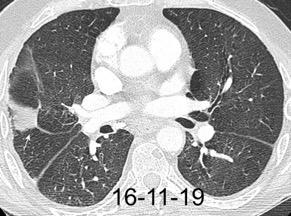

Tromboembolismo pulmonar.

Frecuencia del derrame:

Rx: 32%. TC: 47%

Unilateral. 85%

< 1/3 del hemitórax: 90%

Todos exudados

58% con eritrocitos

21% tabicación lo que causa demora en el diagnóstico

TEP. Empiema pleural. Atelectasia redonda

Porcel JM et al. Analysis of pleural effusions in acute pulmonary embolism: radiological and pleural fluid data from 230 patients. Respirology 2007/ Iguchi T et al. Desquamation of the subpleural lung parenchyma caused by empyema after pulmonary embolism: A case report. Respirol Case Rep. 2022 .